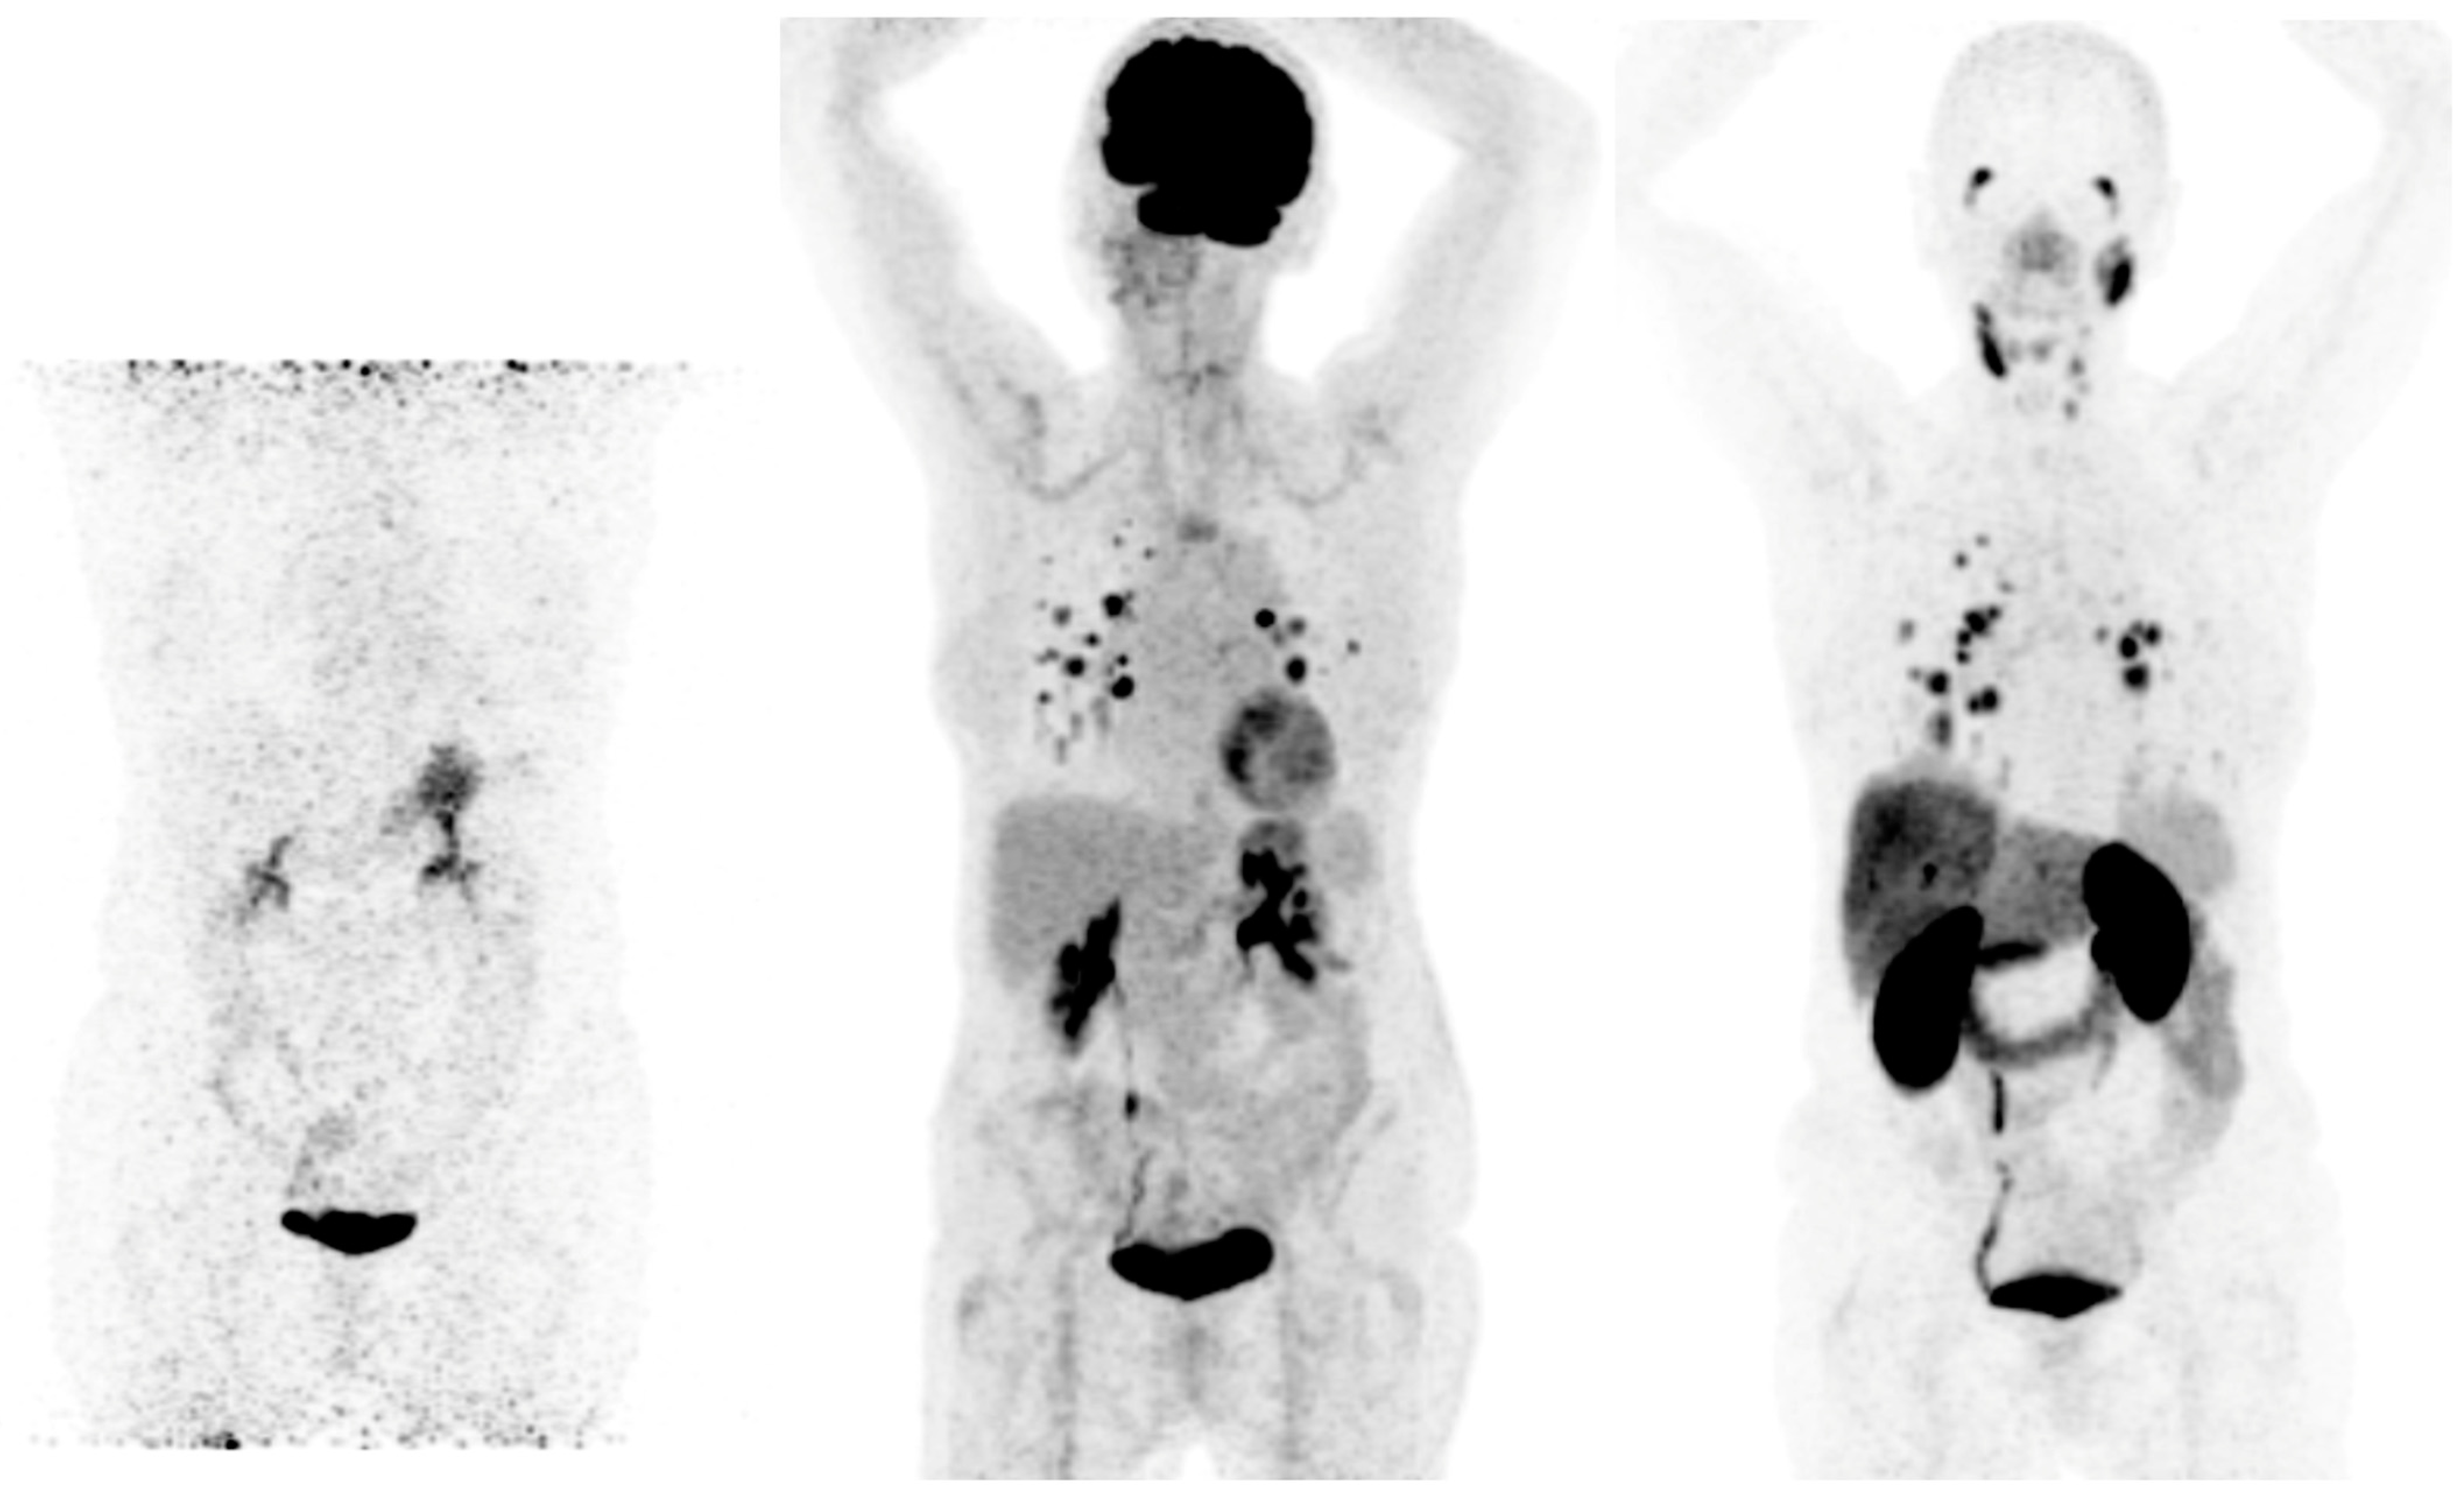

- Feine, U.; Lietzenmayer, R.; Hanke, J.P.; Wohrle, H.; Muller-Schauenburg, W. 18FDG Whole-Body PET in Differentiated Thyroid Carcinoma. Flipflop in Uptake Patterns of 18FDG and 131I. Nuklearmedizin 1995, 34, 127–134. [Google Scholar] [CrossRef]

- Feine, U.; Lietzenmayer, R.; Hanke, J.P.; Held, J.; Wöhrle, H.; Müller-Schauenburg, W. Fluorine-18-FDG and Iodine-131-Iodide Uptake in Thyroid Cancer. J. Nucl. Med. 1996, 37, 1468–1472. [Google Scholar]

- Liu, M.; Cheng, L.; Jin, Y.; Ruan, M.; Sheng, S.; Chen, L. Predicting 131I-Avidity of Metastases from Differentiated Thyroid Cancer Using 18F-FDG PET/CT in Postoperative Patients with Elevated Thyroglobulin. Sci. Rep. 2018, 8, 4352. [Google Scholar] [CrossRef]